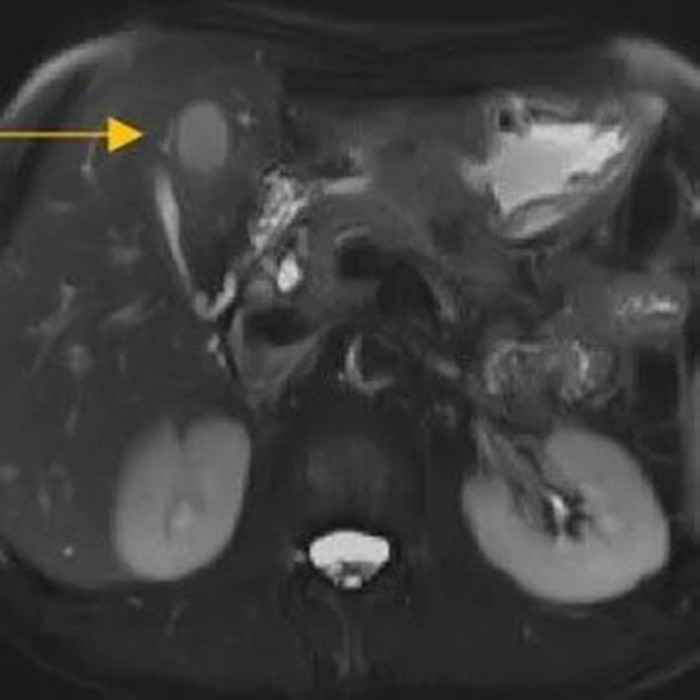

經(jīng)過6個(gè)周期,前后4個(gè)月的治療,周先生再次復(fù)查CT,提示胃部腫瘤,轉(zhuǎn)移的胃旁淋巴結(jié)、肝臟腫瘤都有明顯縮小,營養(yǎng)狀況良好,能正常進(jìn)食,體重增加了6斤,精神狀態(tài)比原先好了很多。

治療前

治療后